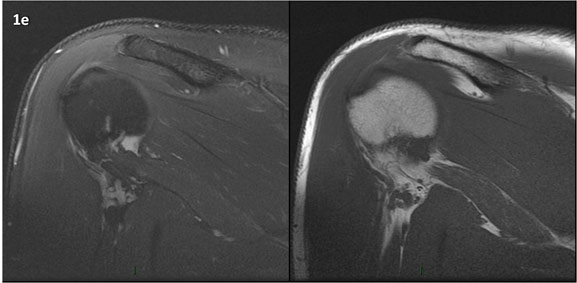

Figura 1 (a-g): Imagens consecutivas de RM no plano coronal nas ponderações DP com supressão de gordura (DP SG) à esquerda e T1 à direita. Clique na seta para passar as imagens.

Figura 1 (a-g)': Imagens consecutivas de RM no plano coronal nas ponderações DP com supressão de gordura (DP SG) à esquerda e T1 à direita mostrando . Clique na seta para passar as imagens.

Figuras 1b’ a 1g’ mostrando atrofia da porção superior do músculo redondo menor (seta salmão), com lipossubstituição mais evidente das mais fibras laterais (seta amarela). As fibras mais inferiores e mediais têm atrofia menos evidente.

Repare que estas alterações não são evidentes nas imagens com supressão de gordura.